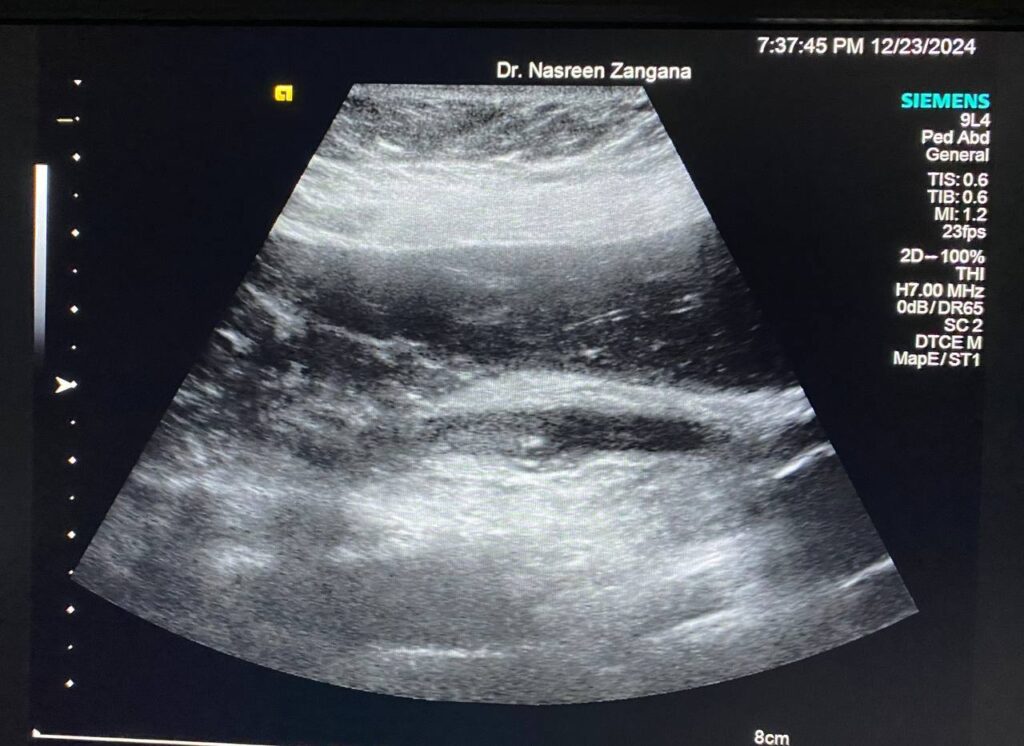

Diffuse dilated common bile duct 7.3mm , with presence of multiple echogenic foci within , the largest 3mm